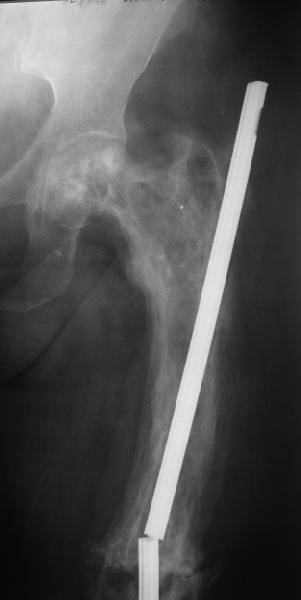

бывали ли у кого-нибудь такие случаи Уважаемые коллеги, вчера прооперировал женщину 60 лет с болезнью Педжета, переломом верхней трети бедра. Выявлена в августе этого года, сломала три дня назад от небольшого усилия. Из сопутствующих болезней лейкоз, сахарный диабет. Бывали ли кого-нибудь такие случаи, чем это все заканчивалось?

Пациент 82 лет, поступил через 5 мес. с несросшимся переломом после открытого интрамедуллярного остеосинтеза. Выполнили реостеосинтез стержнем 12 мм. ( мах. доступного нам в 2003 г.) Через 4 мес динамизация. В течении 2х лет сращения нет, тем не менее конечность опорна (ходит с тростью). От очередного реостеосинтеза отказались из-за сопутств. патологии.